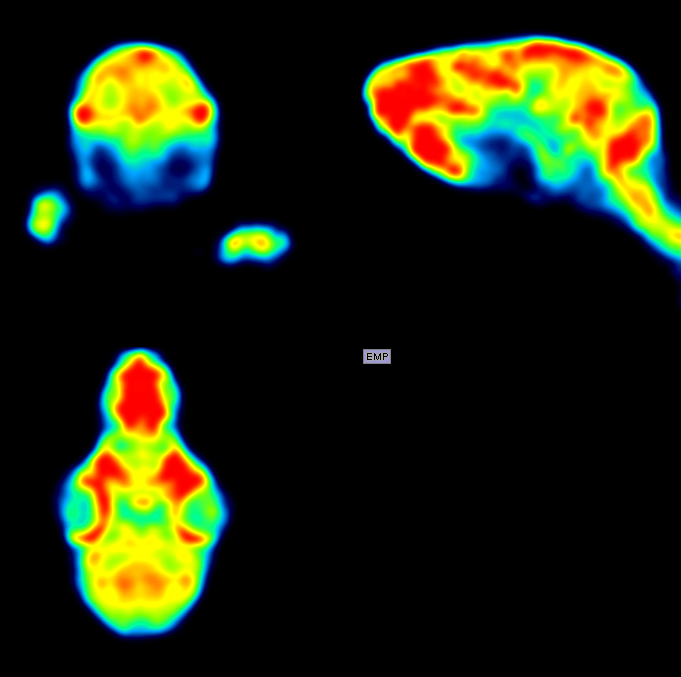

Rabbit with weight of 181g, 18F-FDG NR_iter15_sub_1 4床位拼床

330g 兔子耳缘静脉注射18F-FDG 1.03mCi 60分钟后,每床位采集15分钟,共3床位 / 195g 兔子耳缘静脉注射18F-FDG 190uci 35分钟后,单床位采集2小时